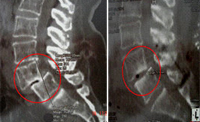

Izquierda: escáner de control post-operatorio de la caja intersomática PEEK

colocada por técnica percutánea. Derecha: doble fusión intervertebral con caja

de PEEK con incisiones de solo 12 mm y bajo anestesia local

Implante endoscópico en L4/L5 para expandir pinzamientos discales sin

necesidad de recurrir a la cirugía abierta. - Vídeos